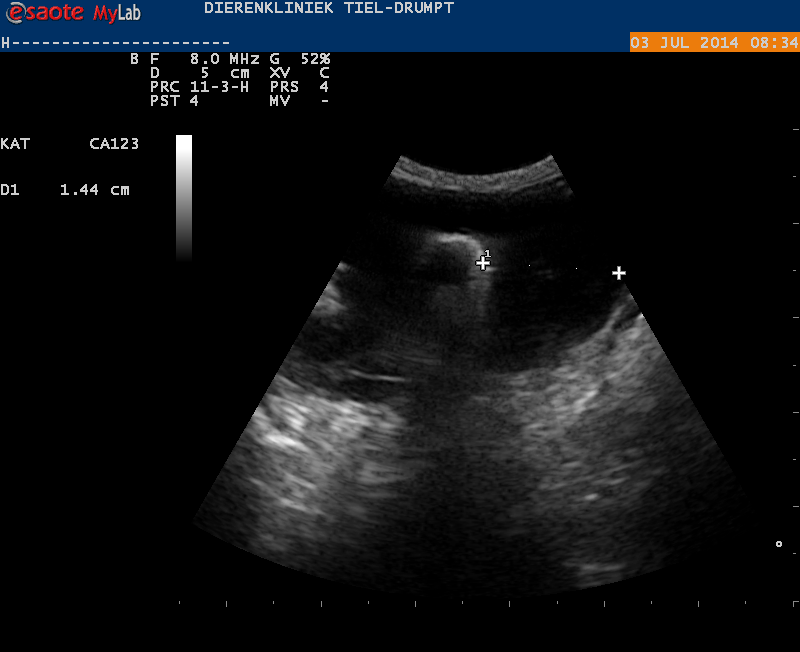

Rochard is een kat die in Frankrijk gevonden is en nu bij zijn baasjes in Zoelen woont. Het is een gezellige kat die wel altijd makkelijk gebraakt heeft. Sinds begin juni 2014 is het braken erger geworden en sinds juli 2014 houdt hij bijna niks meer binnen. Een continu brakende kat is niet gebruikelijk, dus moesten we verder gaan kijken. Omdat we niet zijn gehele voorgeschiedenis weten, zijn we na het klinische onderzoek begonnen met een uitgebreid bloedonderzoek. Hierin vonden we als enige afwijking een iets lager gehalte aan rode bloedcellen. Bij het klinische onderzoek werd door de dierenarts mogelijk een kleine verdikking in de buik gevoeld en we zijn verder gegaan met een echo van de buik. Hierbij vonden we een locale verdikking van de darmwand.

Door middel van het aanprikken van deze wand, hoopten we een diagnose te stellen. Helaas kregen we als uitslag reactief lymfeweefsel, wat voor ons een onverwachte uitslag was.